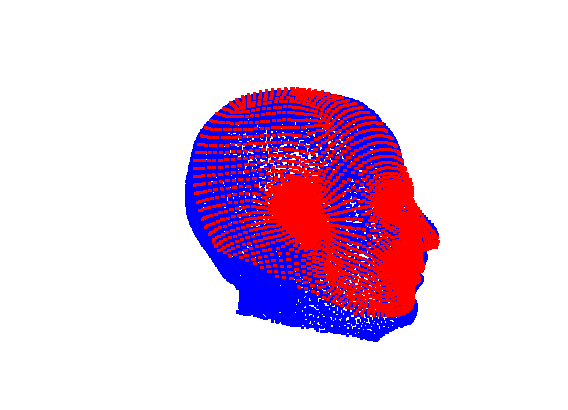

The template mesh is then warped in a global affine sense, as shown in Fig. 27 to minimise the least-squares error between the two sets of landmarks, when the head scan is fixed in its canonical poose. After this initial stage, landmarks and pseudo-landmarks are used in the same way as any other mesh vertex, as they are potentially noisy, as seen in earlier results analysis. This contrasts with Amberg et al’s [11] approach where the influence of landmarks is gradually faded out.

|

|

Following this, OSNR ICP iterates over a set of decreasing mesh stiffnesses (typically 10), until the registration between the template and the scan is below some error or a maximum number of iterations is reached. Figure 28 shows a selection of template warp results. The template appears to be accurately warped onto the scan, at least in the normal direction of the surfaces, it is not possible to see error tangential to the surface. Furthermore, we have noted errors on some scans on the ears. To improve these we need a method of automatically landmarking the ears, which is an area for further work.